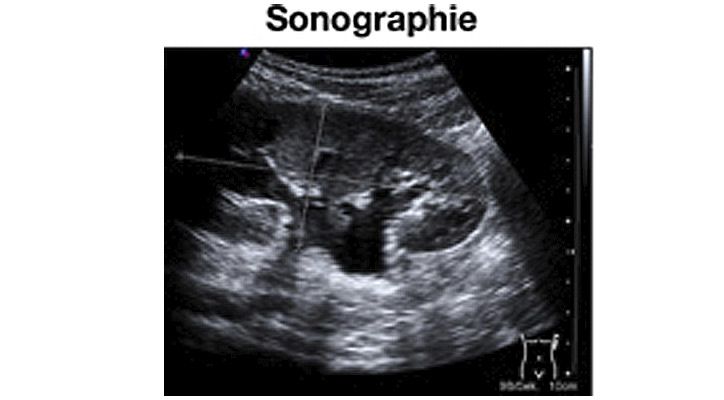

Die Ultraschall-Diagnostik (Sonographie) stellt eine der wichtigsten bildgebenden Verfahren zur Untersuchung der Niere, der ableitenden Harnwege und der Blase dar. Sie ist ohne Strahlenbelastung, tut nicht weh und ist als Kontroll- untersuchung beliebig oft wiederholbar.